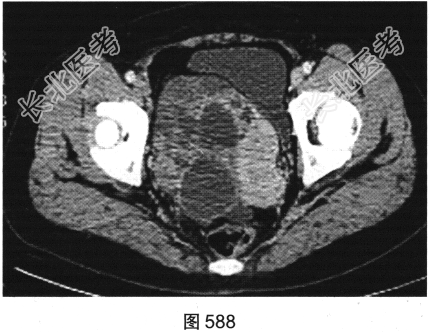

患者女性,38岁,因“间断性下腹部疼痛1周”入院。既往:否认肝炎、结核病史。查体:下腹部压痛。患者行腹部CT检查,见图582~图589。

- 多项选择题2.[提示]患者盆腔CT表现见图590、图591。根据以上两幅盆腔CT图像,可以看到哪些阳性表现( )

A、直肠乙状结肠交界区肠管壁厚,强化不均匀

B、双侧髂血管周围多发结节影,可见强化

C、右侧附件区较大囊实性占位性病变,可见不均匀强化

D、右侧附件区多房囊性占位性病变,未见强化

E、盆底腹膜多发结节状软组织影,可见强化

F、盆腔大量积液

- 多项选择题4.[提示]肠镜活检病理:中分化腺癌。糖链抗原724: 46.46U/ml,癌胚抗原292.61ng/ml, 糖链抗原242:58.13U/ml, 糖链抗原199:65.78U/ml。结合影像、临床、实验室检查及镜检病理结果, 该患者术前诊断应考虑为( )

A、直肠癌,伴肝脏炎性假瘤,右侧附件转移瘤

B、直肠癌,伴肝脏转移瘤及右侧附件转移瘤

C、直肠癌,伴肝脏转移瘤,右侧附件囊腺瘤

D、直肠癌,伴肝脏转移瘤,右侧附件囊腺癌

E、直肠癌,伴肝脏转移瘤.右侧附件子宫内膜异位症

F、直肠癌,伴肝脏炎性假瘤,右侧附件囊腺瘤